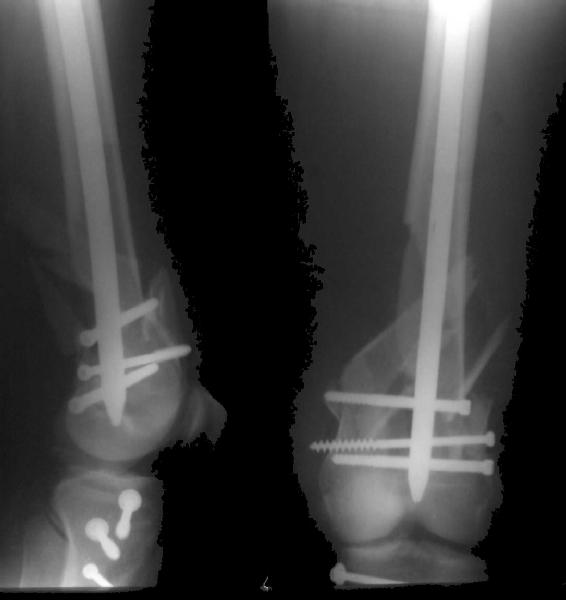

Re: Open supracondylar femur fx

And why LISS is superior here than nail?

Look what we would have done.

Zsolt Balogh 31 Октябрь 2004, 20:46

I would not say that the LISS is superior to the nail. If I would, I had not post original mail. I wanted to generate discussion. Your option is a very viable one. I feel a little bit shaky the distal femur, but it is just gut feeling no science behind it. Any way nice fixation, congarts!